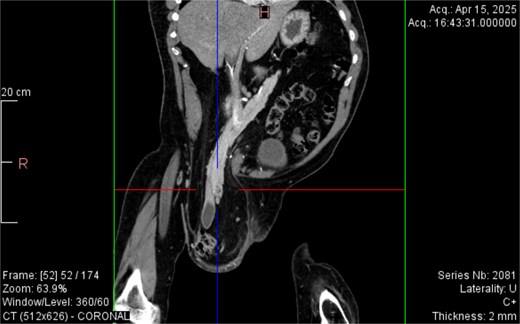

CT imaging (Figs 2–5) revealed a right inguinal hernia containing small bowel loops, ascending colon, the second and third portions of the duodenum, and the pancreatic head. The pancreatic head appeared rotated and displaced inferiorly into the hernia sac, without signs of acute pancreatitis.

Coronal CT view inguinal hernial sac with pancreatic head and D2 and D3 segment of duodenum.

Sagittal CT view inguinal hernial sac with pancreatic head and D2 and D3 segment of duodenum.

Additionally, incidental findings (Fig. 2) included multiple calculi within the left hepatic duct. Though the patient was asymptomatic from a hepatobiliary standpoint, the presence of these stones raised concern for potential biliary stasis.